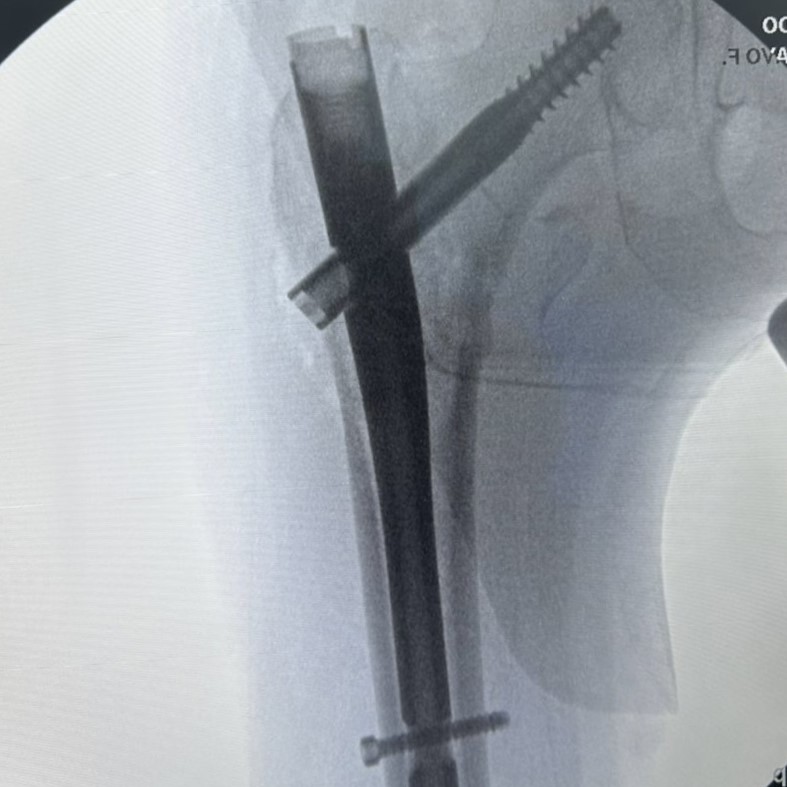

As fraturas do terço proximal do fêmur, que incluem as fraturas de colo do fêmur e as fraturas transtrocantéricas, são lesões graves que afetam a região do quadril e podem ter...